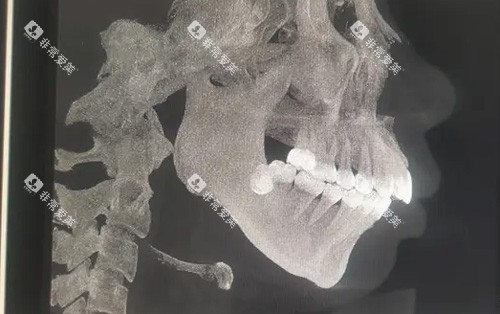

手术必要性需结合患者年龄、畸形类型及全身健康状况综合判断。医生需通过影像学检查和临床评估制定个性化方案,确保手术可靠性和有效性。